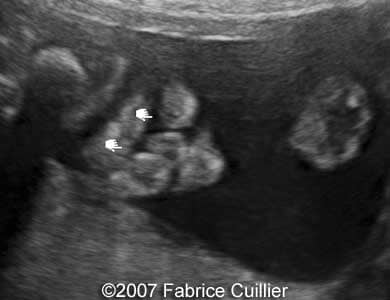

This is an example of bilateral cleft lip

Images 1, 2: 2D tangential planes aligned through the fetal lips showing bilateral cleft of the upper lip.